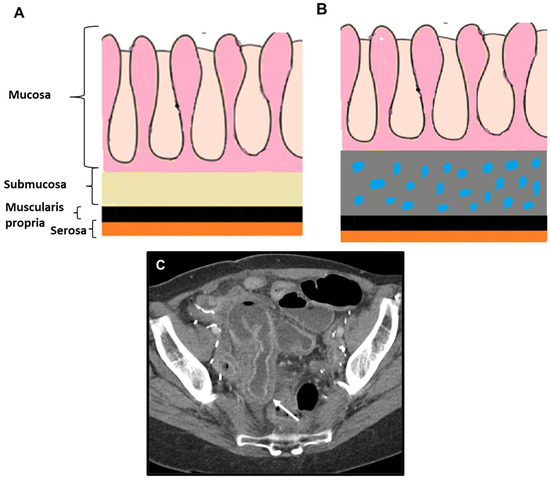

2.2.1. LP-like Metastases to the GI Tract: Imaging Features

Peritoneal Carcinomatosis